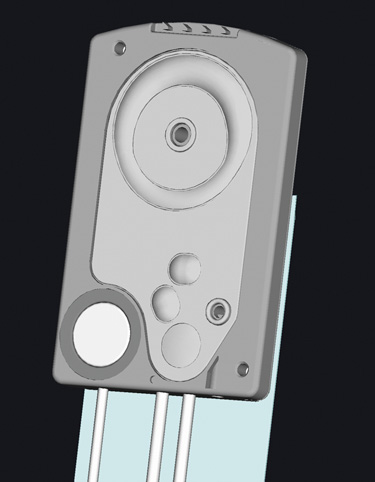

Many patients are most bothered by cataract-induced glare. For these patients, acuity testing under glare situations is indicated. There are several methods to assess visual acuity reduction by glare. The choice of method is often best dictated by the patient's history. If a patient complains of glare problems in the supermarket, or other uniformly illuminated environment, the brightness acuity test can be performed (Mentor Ophthalmics). For this test, the specially illuminated handpiece is held in front of the tested eye using best spectacle correction (Fig. 1). The Snellen acuity is rechecked and can be recorded on each of three light settings.